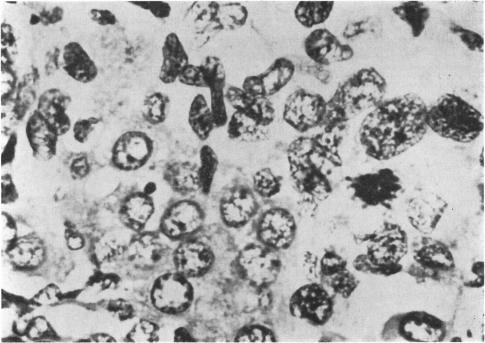

A review of the histology of 332 ovaries from stillbirths and neonatal deaths within the first 28 days of life showed that follicular cysts, lined by granulosa epithelium and having a diameter greater than 1 mm on a microscopical section, were present in 113 infants. In 48 cases multiple cysts were present, while in 65 only a single cyst satisfying the criteria was found. There was an excess number of infants of low birthweight score among those with multiple cysts and the results were highly significant. Cysts, whether single or multiple in distribution, were commoner with increasing gestation, and possibly occurred more commonly in the infants of diabetic mothers and in infants where pregnancy had been complicated by rhesus isoimmunization. The nature of the changes seen in the granulosa lining and theca internal layer surrounding the cysts suggested that these cysts were not some degenerative phenomenon but occured in response to stimulation. It is suggested that homologous changes may occur in the testis of the dysmature male. The possible significance of these findings with regard to hormonal imbalance in the growth-retarded infant is considered, and the need for closer attention to endocrine function in these infants stressed.

对332例死产儿及出生后28天内新生儿死亡的卵巢进行组织学检查,结果显示,在113例婴儿的卵巢中发现有滤泡囊肿,显微镜下可见囊肿内衬颗粒上皮,直径大于1mm。其中48例为多发性囊肿,65例仅发现1个符合标准的囊肿。多发性囊肿患儿中低体重评分婴儿数量过多,结果具有高度显著性。囊肿无论单发还是多发,均随孕周增加而更常见,且可能在糖尿病母亲的婴儿以及因恒河猴血型免疫而使妊娠复杂化的婴儿中更常见。囊肿周围颗粒层内衬及卵泡内膜层的变化性质表明,这些囊肿并非某种退行性现象,而是对刺激的反应。有人提出,在发育不成熟的男性睾丸中可能会出现类似变化。文中考虑了这些发现对于生长发育迟缓婴儿激素失衡的可能意义,并强调需要更加密切关注这些婴儿的内分泌功能。